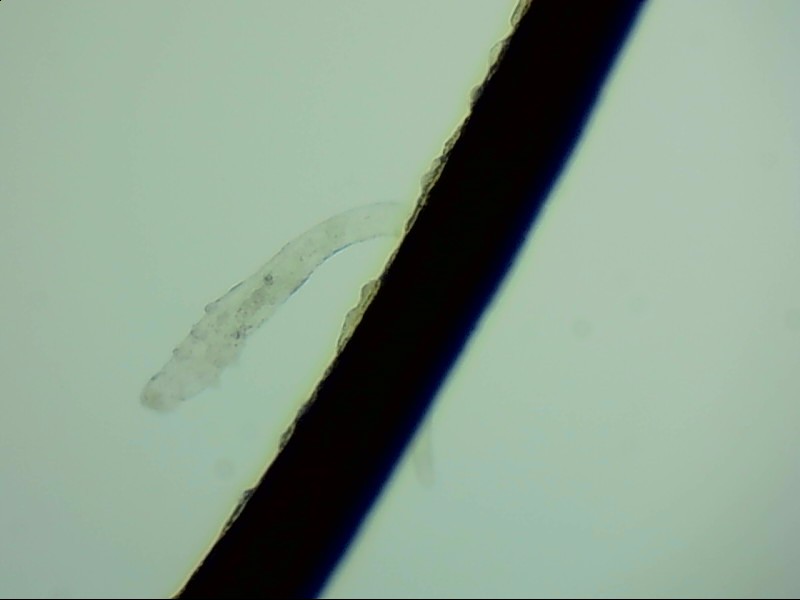

睫毛根部的蠕形螨

蠕形螨是自然界中常見(jiàn)的生物,在人的身上有兩種,分別是毛囊蠕形螨和脂質(zhì)蠕形螨,人身上以毛囊蠕形螨為主,它們主要生活在睫毛根部。

在電子顯微鏡下我們才能看到睫毛根部的一只只蠕形螨,它們不但會(huì)啃食睫毛根部附近的油脂,讓睫毛長(zhǎng)的東倒西歪,還會(huì)給眼睛帶來(lái)發(fā)癢、干澀、瞼緣炎充血、在睫毛根部留下袖套狀的分泌物等各種各樣的癥狀,拉低患者的生活質(zhì)量。